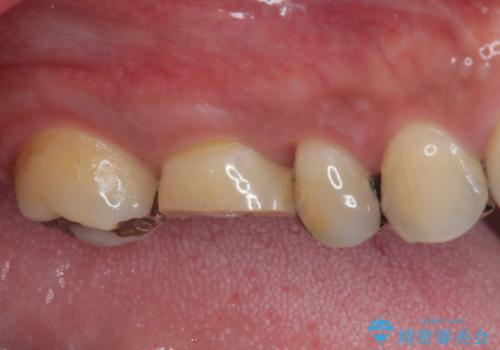

治療途中の奥歯 オールセラミッククラウンでのむし歯治療

- 近医にて治療を行っていたものの、痛みがなかなか引かないとのことで転院されてきた患者様です。

上下で接触しないように削られていたため、日常生活で痛みを感じることはありませんでしたが、歯を叩くと痛みを感じる状態でした。

前医ではラバーダムの装着をされていない状態で根管治療を行っていたようで、その他の器具や処置も無菌的環境下であったとは考えにくいため、それが痛みがなかなか引かない原因の一つであると考えられました。

根管治療後に痛みの消失を確認し、オールセラミッククラウンにて補綴治療を行うこととしました。